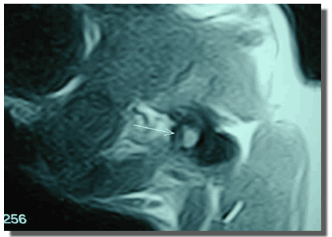

El diagnóstico de las patologías vestibulares centrales requiere métodos de diagnóstico más sofisticados (Figura 10).

Figura 10: RMN de cráneo y cerebro en incidencia L-L (A), y en incidencia D-V (B). Obsérvese la masa de tejido blando en la cavidad del oído medio, compatible con la presencia de pólipos.

La resonancia magnética (RM) es ideal para el estudio del SNC. Es mucho más sensible que la TAC para la evaluación de la fosa posterior cerebral y del tronco encefálico, ya que no es susceptible a los artificios que produce la atenuación de la emisión radiográfica por la porción petrosa del hueso temporal. El análisis del líquido cefalorraquídeo (LCR) puede ser útil en la caracterización de la patología, y es diagnóstico cuando se detectan organismos (por ejemplo Cryptococcus sp) o células tumorales. También puede ser remitido para realizar pruebas serológicas (toxoplasmosis) o cultivo y antibiograma.